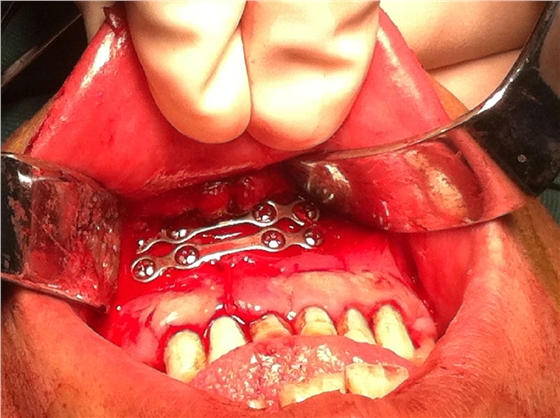

入院后全麻下手術治療,左側下頜骨囊腫較大,術前考慮病理性骨折可能,準備鈦釘鈦板固定,術中摘除囊腫后,發(fā)現(xiàn)下頜骨下緣骨量尚可,未給予固定。術后病理診斷為下頜骨角化囊腫,考慮到患者可能為基底細胞癌綜合征,術中切除頸部皮膚痣兩處,術后病理診斷為:皮膚痣,排除基底細胞癌綜合征?;颊哂凶髠鹊诹吖欠植胬?,綜合以上特征,最終診斷為多發(fā)性頜骨囊腫綜合征。